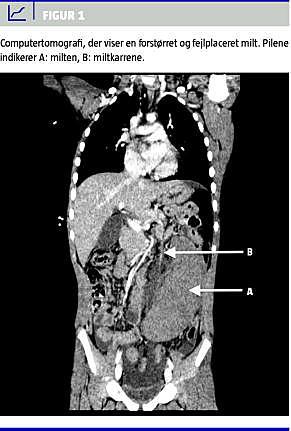

På operationsstuen blev drengen lagt i generel anæstesi, hvorefter man observerede en stor, frit forskydelig proces til venstre i abdomen. Der blev på denne baggrund bestilt en akut ultralydskanning (UL). Da denne var inkonklusiv, og da flowforholdene ikke kunne ikke afklares, fulgte man op med en computertomografi, som viste en forstørret milt, en muligvis fortykket appendix og fri væske i det lille bækken (Figur 1 ). Paraklinisk var der følgende niveauer: C-reaktivt protein over 200 mg/l, leukocytter 17 × 10 9 /l, hæmoglobin 5,3 mM, trombocytter 103 × 10 9 /l, K+ 5,7 mM, Na + 131 mM og spontan plasma protrombintid på 46%.